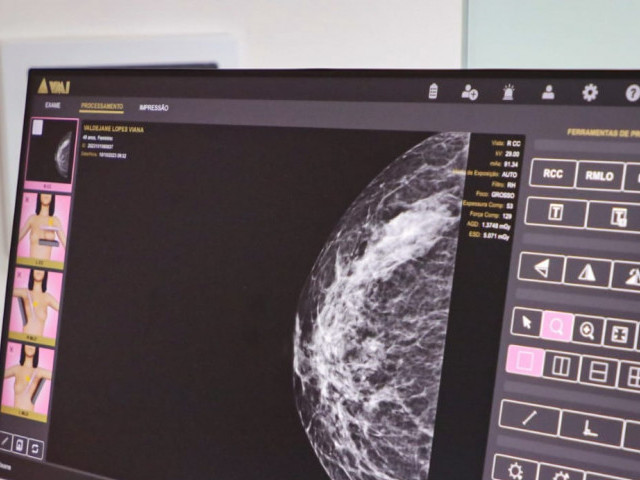

Além disso, vale ressaltar que mulheres com idade entre 40 e 69 anos devem realizar a mamografia, utilizada para o rastreamento do câncer de mama. Esse exame é disponível principalmente para essa faixa etária devido a maior predominância de casos.

Até o mês de setembro de 2023, o Caism realizou 4.595 exames de mamografia e 139 magnificações mamárias (exame complementar à mamografia). Já em 2022, foram realizadas 5.011 mamografias e 129 magnificações mamárias. A expectativa é que os números de 2023 superem o ano anterior.

E para apoiar a campanha Outubro Rosa, mês de conscientização da doença, o serviço ampliou a oferta de exames de mamografia e pretende atingir a meta de realização de 360 exames/semana e 1.440 exames/mês, levando mais mulheres a serem assistidas pelo Caism.